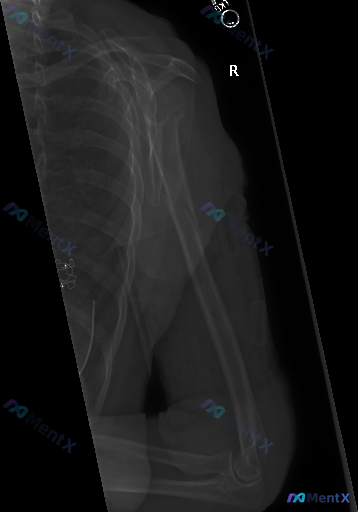

检查类型: 右侧肩关节及肱骨全长X线平片(正位/前后位投影)

- 骨骼方面:右侧肱骨干中下段可见清晰锐利的骨折线,断端有明显错位,远端向外侧移位且存在重叠,提示短缩畸形;肩胛骨、锁骨、肱骨头、肱骨远端与尺桡骨近端构成的关节关系尚可,未见明显骨质破坏或脱位。

- 软组织方面:骨折断端周围软组织轮廓略显模糊,符合肿胀表现;腋下及上臂周围未见明确钙化或游离气体影。

- 其他:上臂外侧可见与皮肤接触的金属或高密度条带状影,类似外固定架/支具痕迹;图像包含的部分胸廓侧缘未见明显异常。